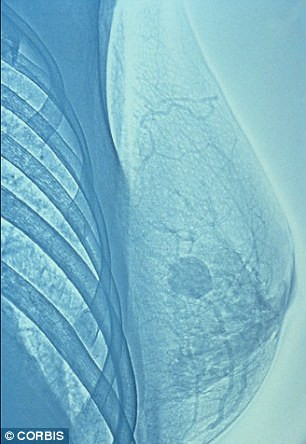

Một nhóm các nhà khoa học tới từ trường cao đẳng Hoàng đế London (Imperial College London) đã phân tích mẫu máu của hơn 2.600 phụ nữ đến từ Anh, Na Uy, Australia và Italy để kiểm tra sự thay đổi ADN của tế bào bạch cầu. Trải qua rất nhiều các công trình nghiên cứu trong vòng 9 năm, họ phát hiện ra rằng những người có nồng độ chất methyl trong bạch cầu ít hơn thường bị bệnh ung thư vú.

| Bằng cách kiểm tra nồng độ methyl trong bạch cầu, bác sĩ có thể xác định được nguy cơ bị ung thư vú của người bệnh. |

Quá trình tạo methyl trong ADN là một quá trình cần thiết cho sự phát triển của các tế bào. Tuy nhiên, nồng độ của chất này có thể bị ảnh hưởng bởi các tác nhân bên ngoài như rượu.

Từ đó, các nhà khoa học đưa ra kết luận rằng thường xuyên kiểm tra nồng độ methyl trong bạch cầu sẽ giúp mọi người thay đổi được lối sống, từ đó ngăn chặn sự phát triển của bệnh ung thư vú.